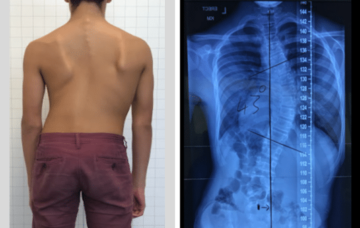

اعوجاج العمود الفقري الشديد عند الأطفال: مخاطر تركه دون علاج يعاني بعض الأطفال والمراهقين من اعوجاج العمود الفقري بدرجات مختلفة، لكن القلق الحقيقي يبدأ عندما يصبح الاعوجاج شديدًا ويُترك دون متابعة أو علاج مناسب.

تأثير عدم علاج اعوجاج العمود الفقري : كيف يؤثر على الجسم والثقة بالنفس والحياة اليومية يعاني بعض المراهقين من انحناء بسيط أو متوسط في العمود الفقري، ويعرف أحيانًا بـ الجنف المراهقي مجهول السبب. يتساءل

ما هو اعوجاج العمود الفقري (الجنف)؟ الأسباب، الأعراض، وأحدث طرق العلاج اعوجاج العمود الفقري، المعروف طبيًا باسم الجنف، هو انحناء غير طبيعي في العمود الفقري نحو أحد الجانبين (يمين أو يسار). يظهر هذا الاعوجاج

هل ممكن أن يزداد أعوجاج العمود الفقري فجأة عند الأطفال والمراهقين؟ أعوجاج العمود الفقري، أو ما يعرف طبيًا بالجنف، هو انحناء غير طبيعي في العمود الفقري يظهر عادةً في مرحلة الطفولة أو المراهقة. سؤال